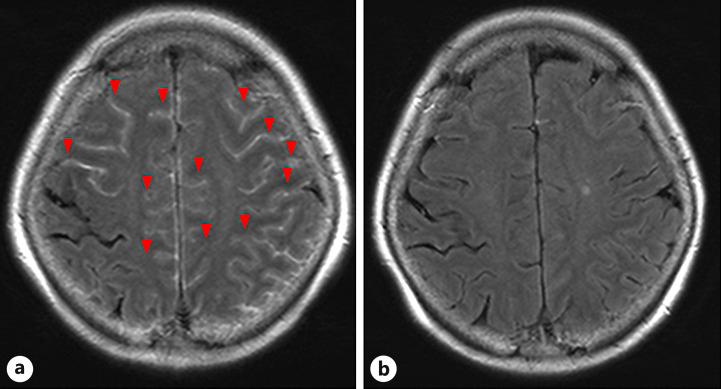

A 74-year-old woman diagnosed with advanced HCC and treated with first-line atezolizumab plus bevacizumab developed anorexia, fatigue, and fever, after three treatment cycles. Cerebrospinal fluid examination showed slightly increased cell count and protein level but no infection or malignancy. Contrast enhancement along the cerebral sulcus was evident in contrast-enhanced magnetic resonance imaging, and the patient was diagnosed with aseptic meningitis associated with atezolizumab. Steroid therapy soon improved her clinical symptoms, and the contrast enhancement along the cerebral sulcus disappeared.

一名74岁女性被诊断为晚期HCC并接受一线阿替利珠单抗联合贝伐单抗治疗,在三个治疗周期后出现厌食、疲劳和发热。脑脊液检查显示细胞计数和蛋白水平略有升高,但未发现感染或恶性肿瘤。对比增强磁共振成像显示脑沟有明显的对比增强,患者被诊断为与阿替利珠单抗相关的无菌性脑膜炎。类固醇治疗很快改善了她的临床症状,脑沟的对比增强消失。